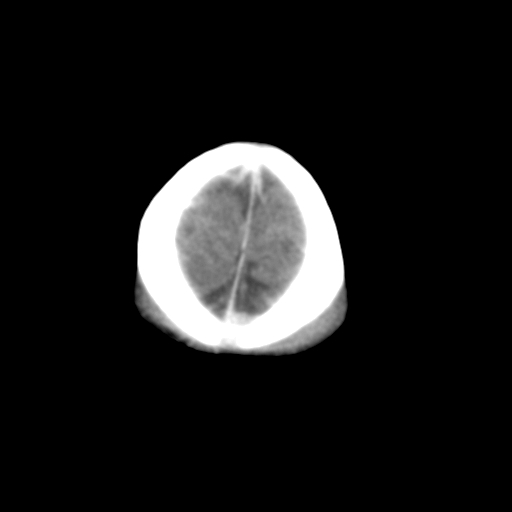

新生儿女2天,有窒息史,经抢救好转!白质最低ct值>23hu,请教各位老师:是否有出血?是否合并缺氧脑病?谢谢!

hie、蛛网膜下腔出血,皮下血舯。

双侧额叶白质低,白质ct值低于18hu可以考虑水肿改变

后纵裂密度高,前纵裂密度低,比较来说应该考虑有蛛网膜下腔出血

空三角征,蛛网膜下腔出血。